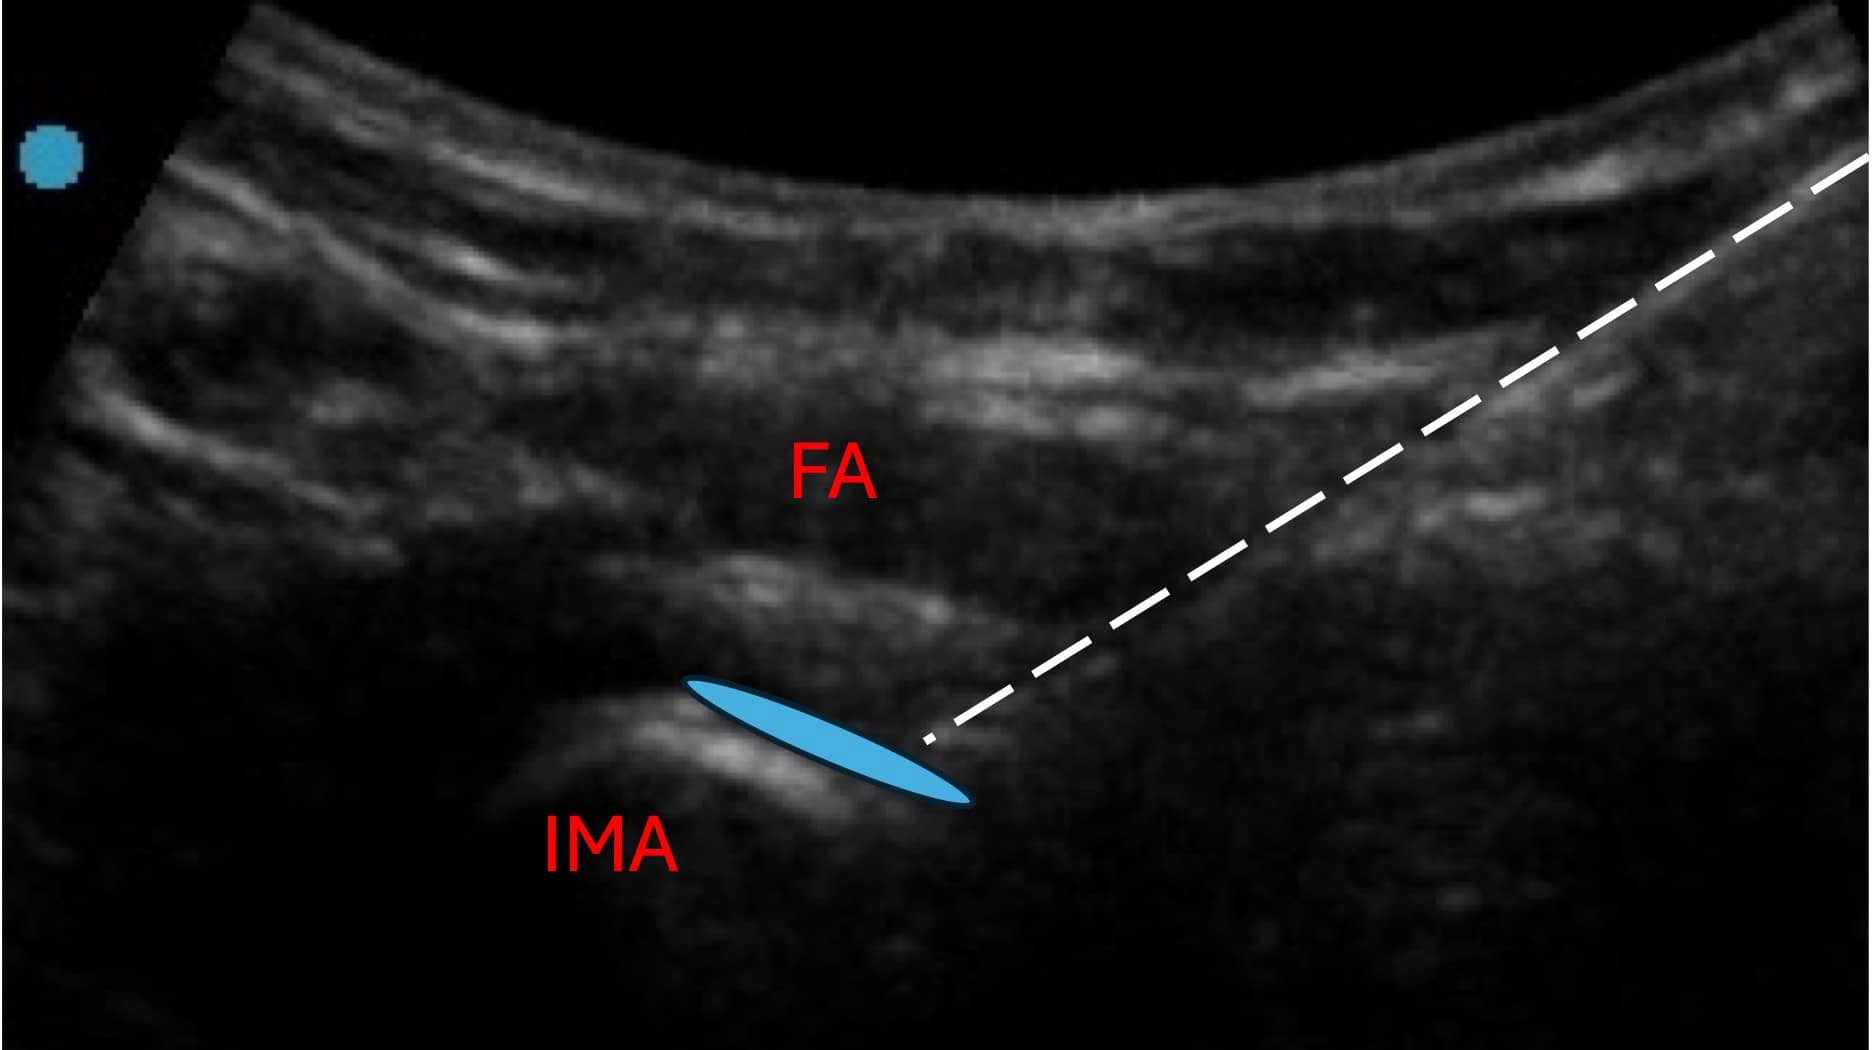

Sequential lesion along the target zone can also be performed easily by withdrawing the RF cannula more proximally. The articular branches of the accessory obturator nerve are also best targeted along the IPE and are typically captured via the lesioning approach described for the articular branches of the femoral nerve. The target for the articular branches of the obturator nerve can be visualized along the inferomedial acetabulum (IMA). This view is typically first achieved through the hip intra-articular view sonographically. The probe is then translated inferomedially to visualize the inferomedial acetabulum.

IPE = iliopublic eminence, FA = femoral artery

Benefits of ultrasound use in hip denervation include improved visualization of the vasculature, neural, and important musculoskeletal structures when traversing the needle towards the target zone. In targeting the IPE where the articular branch of the femoral nerve and the accessory obturator nerves lie, care should be taken to avoid RF cannula puncture of the psoas tendon, which otherwise may result in injury of the tendon and significant post-procedure pain (see Figure 2).6 In targeting the inferomedial acetabulum where the articular branches of the obturator nerve lie, care should be taken to avoid RF cannula through the femoral artery and femoral nerve as well as adjacent vasculature, such as the external pudendal artery.6 Although the rates of femoral artery and nerve injuries are not well known for hip denervation, a sonographic approach serves to reduce the risks of inadvertent injury (see Figure 3).